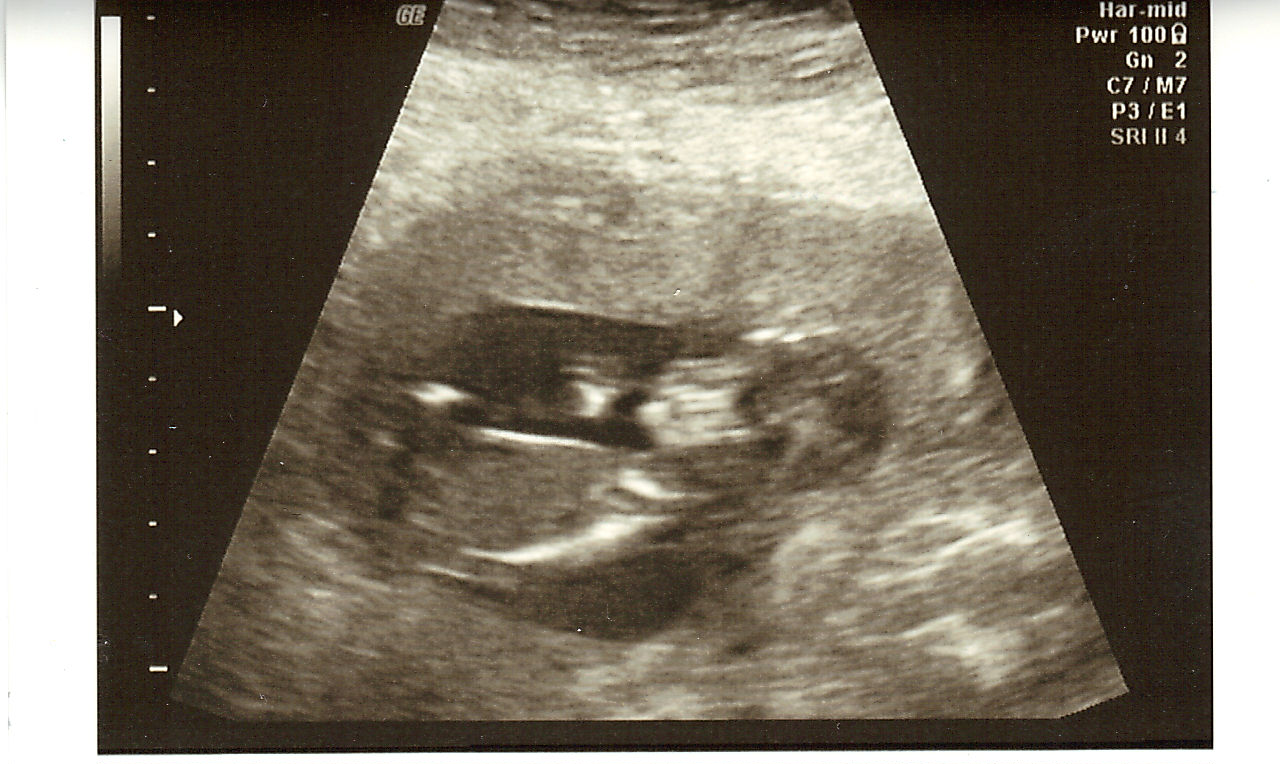

but first a photowhore of Sprout

Oh yeah throughout all of this Sprout's heart rate was 143-144 and still wouldn't show us the goods when I had my ultra sound.